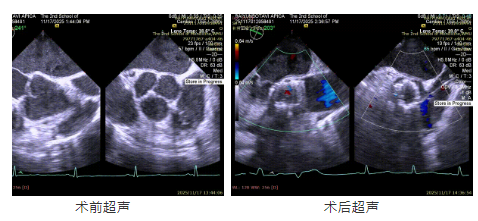

患者為78歲男性,因“活動后胸悶氣短1年,加重1月”入院。既往合并高血壓,慢性腎功能不全3期,慢性骨髓增生性疾病等。術前超聲提示主動脈瓣重度關閉不全伴輕度狹窄,左室擴大,左室舒張功能減低但收縮功能尚可。

患者主動脈瓣重度反流糾正,術后無反流、無瓣周漏。術后心臟彩超顯示人工生物瓣啟閉良好,平均跨瓣壓差3mmHg,流速正常?;颊呋謴颓闆r良好,心臟功能得到顯著改善。